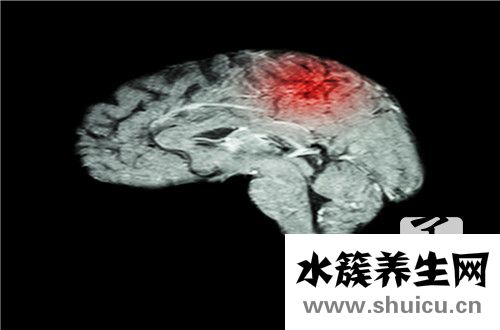

垂體瘤是在大腦中生長的腫瘤。 大多數(shù)人在聽到大腦腫瘤時(shí)通常會非常擔(dān)心和恐懼。 實(shí)際上,由于性別差異,垂體瘤的出現(xiàn)會有所不同,但是患有垂體瘤的女性人群通常超過男性。 垂體瘤是一種非常嚴(yán)重的疾病,將嚴(yán)重影響患者的身心健康和日常生活。 垂體瘤的最佳治療方法是什么?

垂體瘤是一種產(chǎn)生在腦垂體上的腫瘤,也叫腦垂體囊腺瘤,是普遍的神經(jīng)內(nèi)分泌腫瘤中的一種,非常值得慶興的是,絕大部分的腦垂體囊腺瘤全是良好腫瘤。由于腦垂體在內(nèi)分泌系統(tǒng)中具有十分關(guān)鍵的功效,它根據(jù)代謝很多促生長激素來管控人體內(nèi)的諸多女性激素,所以說,假如腦垂體出現(xiàn)了出現(xiàn)異常,會造成 腦垂體代謝的生長激素產(chǎn)生改變,也便會影響身體很多生長激素的生成及作用,假如影響雌激素的水準(zhǔn),便會影響生孕作用,可是也是有一部分垂體瘤是無多功能性的,要想要知道得的是哪樣垂體瘤,就一定要根據(jù)查驗(yàn)之后明確。所以說,針對長了垂體瘤的患者而言,是十分比較嚴(yán)重的。

1、用藥治療,因?yàn)樗目捎萌巳悍秶鷱V被廣泛應(yīng)用。醫(yī)治特性為身體消化吸收快,藥品絕大多數(shù)進(jìn)到頭部,可是相對性的斷藥后可能出現(xiàn)高泌乳素尿癥發(fā)作和腫瘤容積再度擴(kuò)大,因此務(wù)必長期性吃藥,不可以斷藥。

2、手術(shù)醫(yī)治,分成腦部手術(shù)和經(jīng)蝶竇手術(shù)治療二種,一種是經(jīng)額下摘除腫瘤,一種是借鼻孔安全通道直通腦垂體腫瘤。因?yàn)槭中g(shù)治療實(shí)際操作繁雜,技術(shù)水平高,風(fēng)險(xiǎn)性很大,會殘余腫瘤組織,且復(fù)發(fā)較高,不可以反復(fù)醫(yī)治。

3、射波刀醫(yī)治,射波刀是選用即時(shí)影象正確引導(dǎo)技術(shù)性的機(jī)器設(shè)備,醫(yī)治中運(yùn)用人體框架構(gòu)造作為靶區(qū)定項(xiàng)和射束調(diào)整的系統(tǒng),在“手術(shù)治療”全過程里能實(shí)時(shí)追蹤患者吸氣對身體疾病做動態(tài)性直射的放射性外科神器。影象正確引導(dǎo)技術(shù)性包括了2組頂角(X光90度交叉式)X-光影象顯影液器,在“手術(shù)治療”全過程中即時(shí)檢驗(yàn)X光影象上靶區(qū)的偏移,并對隨吸氣而健身運(yùn)動的胸腹部腫瘤作動態(tài)性直射,開展即時(shí)賠償調(diào)整,保證 “手術(shù)治療”的精確性,進(jìn)而使放射線徹底直射在腫瘤上,不容易損害周邊別的組織組織,具有了維護(hù)一切正常組織的功效,因此病人醫(yī)治完沒什么出現(xiàn)異常反映,副作用更小。